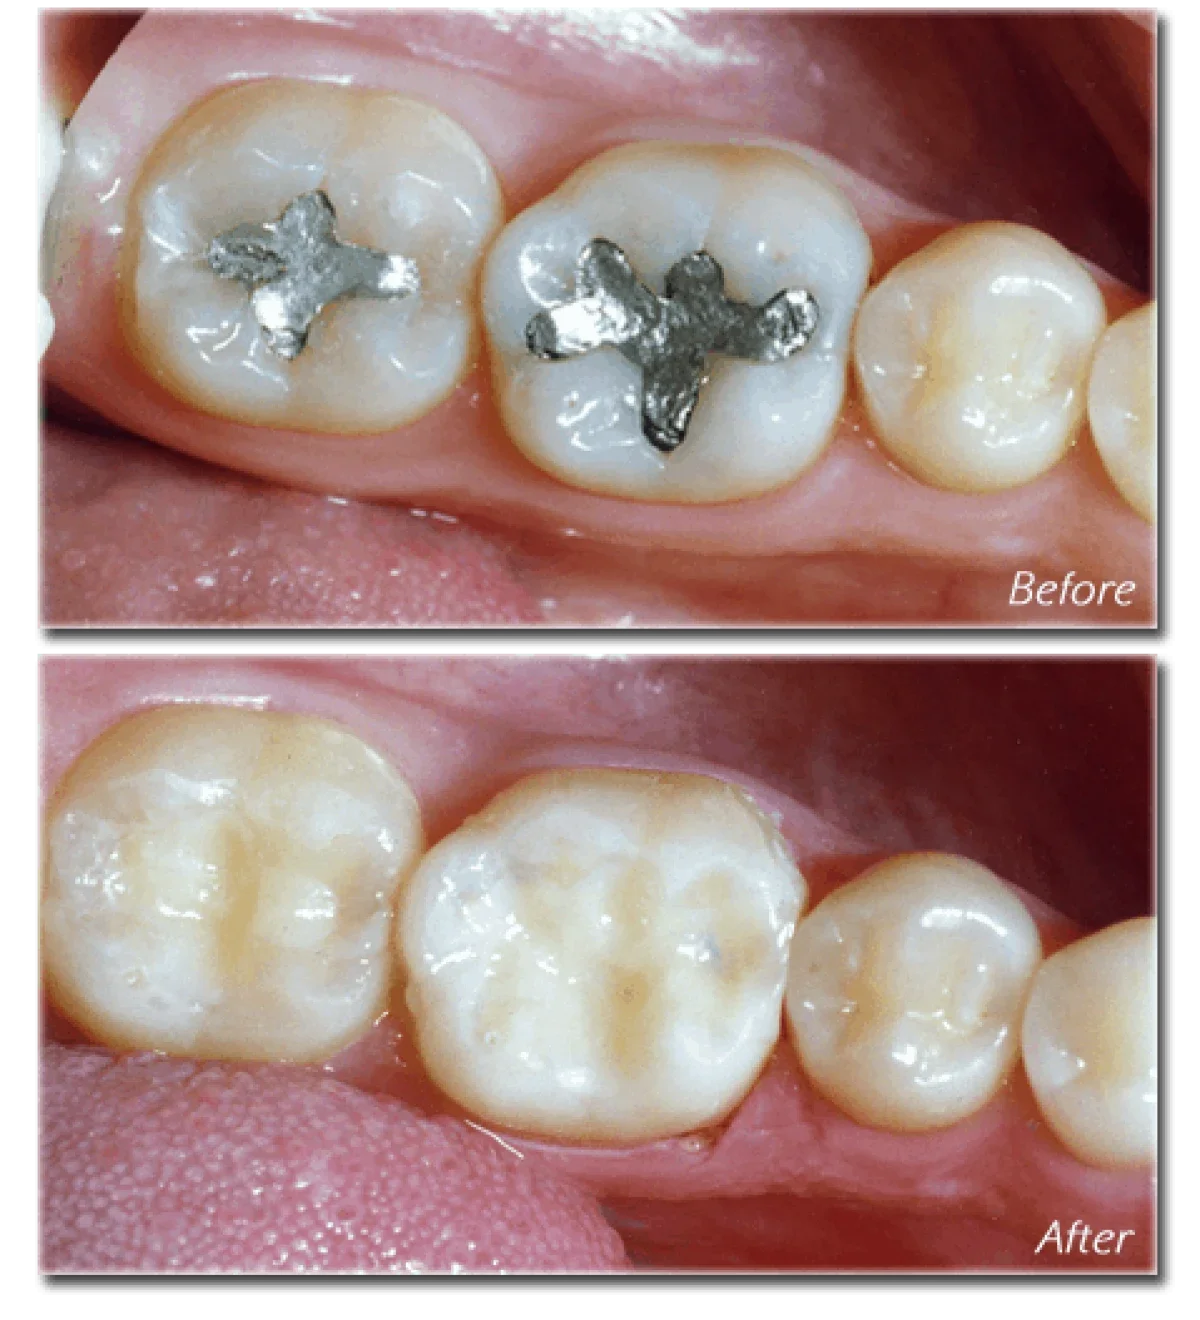

General Dentistry - Everyone knows that fillings, cleaning and simple extractions, Fluoride treatments fissure sealants come under General dentistry. At PDS we pride ourselves in having banned the use amalgams which are the mercur” filled metal filli

Everyone knows that fillings, cleaning and simple extractions, Fluoride treatments fissure sealants come under General dentistry. At PDS we pride ourselves in having banned the use amalgams which are the mercur” filled metal fillings. If at all the School Dental Service tells you that your child needs an amalgam filling, put your foot down and bring the child to us for a tooth coloured resin filling.